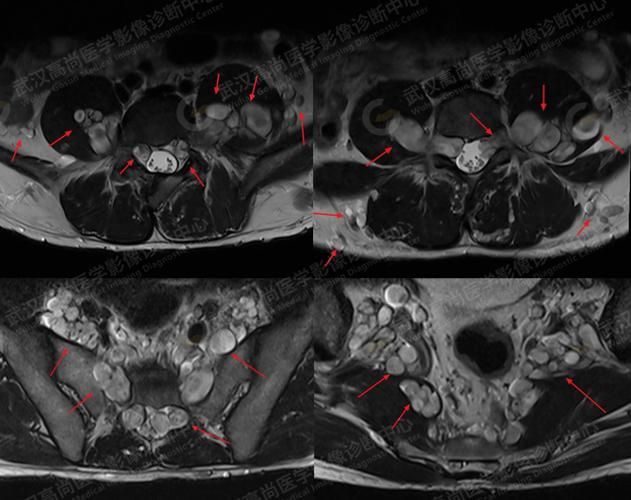

- 神經纖維瘤病Ⅰ型(NF1)診斷案例

患者為52歲男性,主訴反復頭暈1月余,神經系統查體無陽性體征。MRI顯示:透明隔、第三腦室旁、雙側丘腦、中腦、右側顳葉內側多發片狀異常信號,T1WI呈低信號,T2WI呈高信號,增強后均勻強化;頭皮多發結節狀異常信號,增強顯著強化。結合臨床特征——多發性神經纖維瘤與咖啡牛奶斑,最終確診為神經纖維瘤病Ⅰ型。該病為常染色體顯性遺傳,70%~90%患者T2WI可見局灶性高信號病灶,常累及視覺通路、腦干及白質,無占位效應,但可伴血管發育異常(如煙霧病)。影像學診斷關鍵在于識別“無占位性高信號灶”與皮膚色素斑的共存。